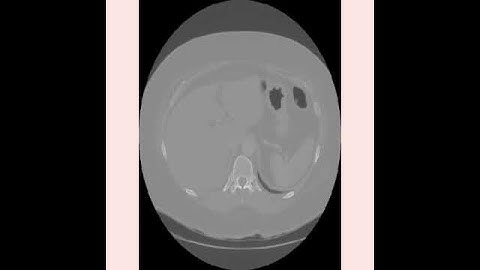

Final Year Projects | A Computer Aided Diagnosis System for Lung Cancer Detection using Machine